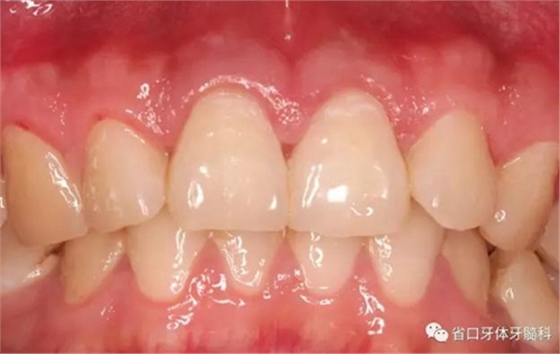

圖1:術(shù)前口內(nèi)照